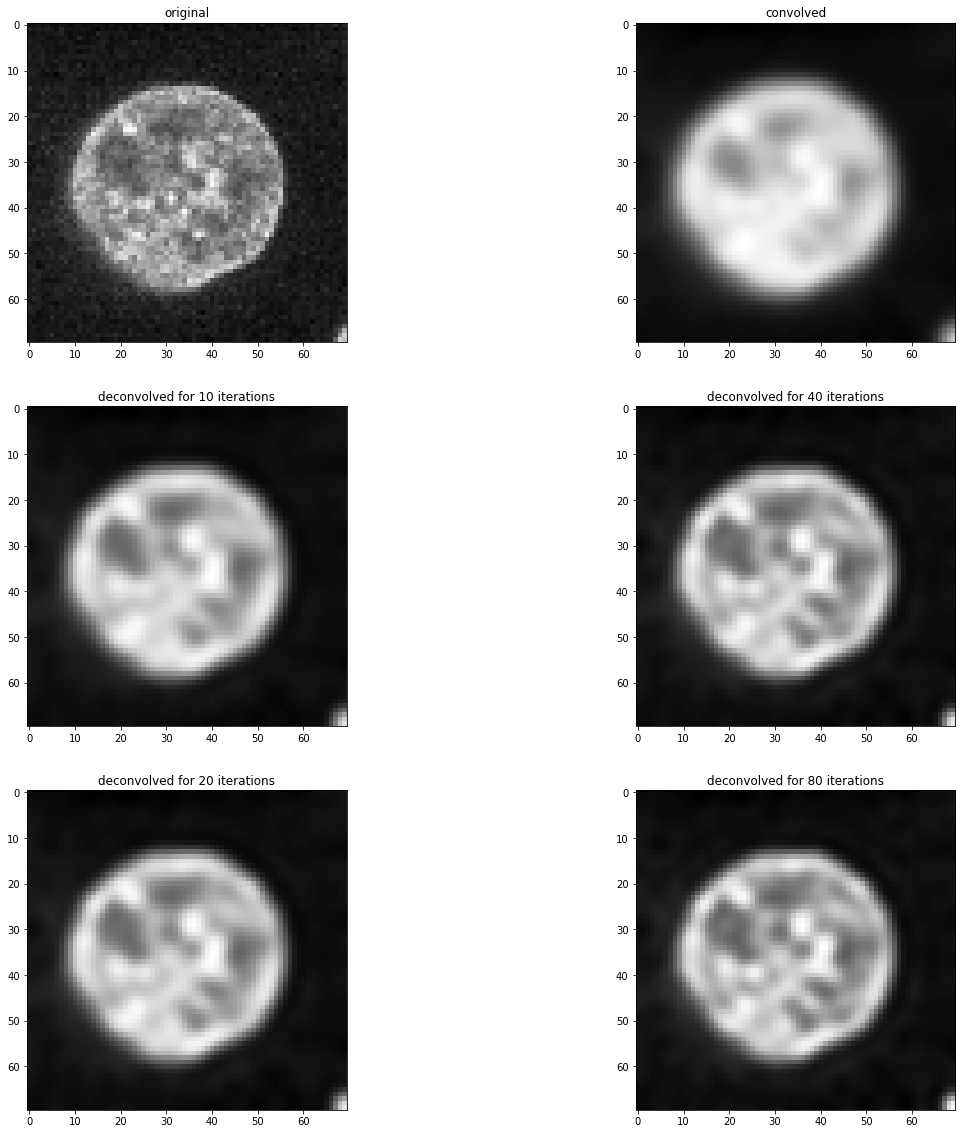

为了演示卷积和反卷积,我们暂时假设这张显示细胞核的图像反映了生物样本中的实际情况。

image = cells3d()[30,1,120:190,80:150]

imshow(image)

如你所见,这个反卷积后的图像与上面显示的原始图像不相等。反卷积不是魔法。它是一个图像处理滤波器,所有滤波器都有局限性。此外,对于这个反卷积算法,结果取决于迭代次数。我们可以通过测试不同的值来经验性地找到这个参数的好的数值。

fig, axs = plt.subplots(3, 2, figsize=(20,20))

imshow(image, plot=axs[0, 0])

axs[0,0].set_title("原始图像")

imshow(convolved, plot=axs[0, 1])

axs[0,1].set_title("卷积后")

for i, number_of_iterations in enumerate([10, 20, 40, 80]):

deconvolved = richardson_lucy_deconvolution(convolved, psf, number_of_iterations)

axis = axs[(i) % 2 + 1, int((i) / 2)]

imshow(deconvolved, plot=axis)

axis.set_title("反卷积 " + str(number_of_iterations) + " 次迭代")